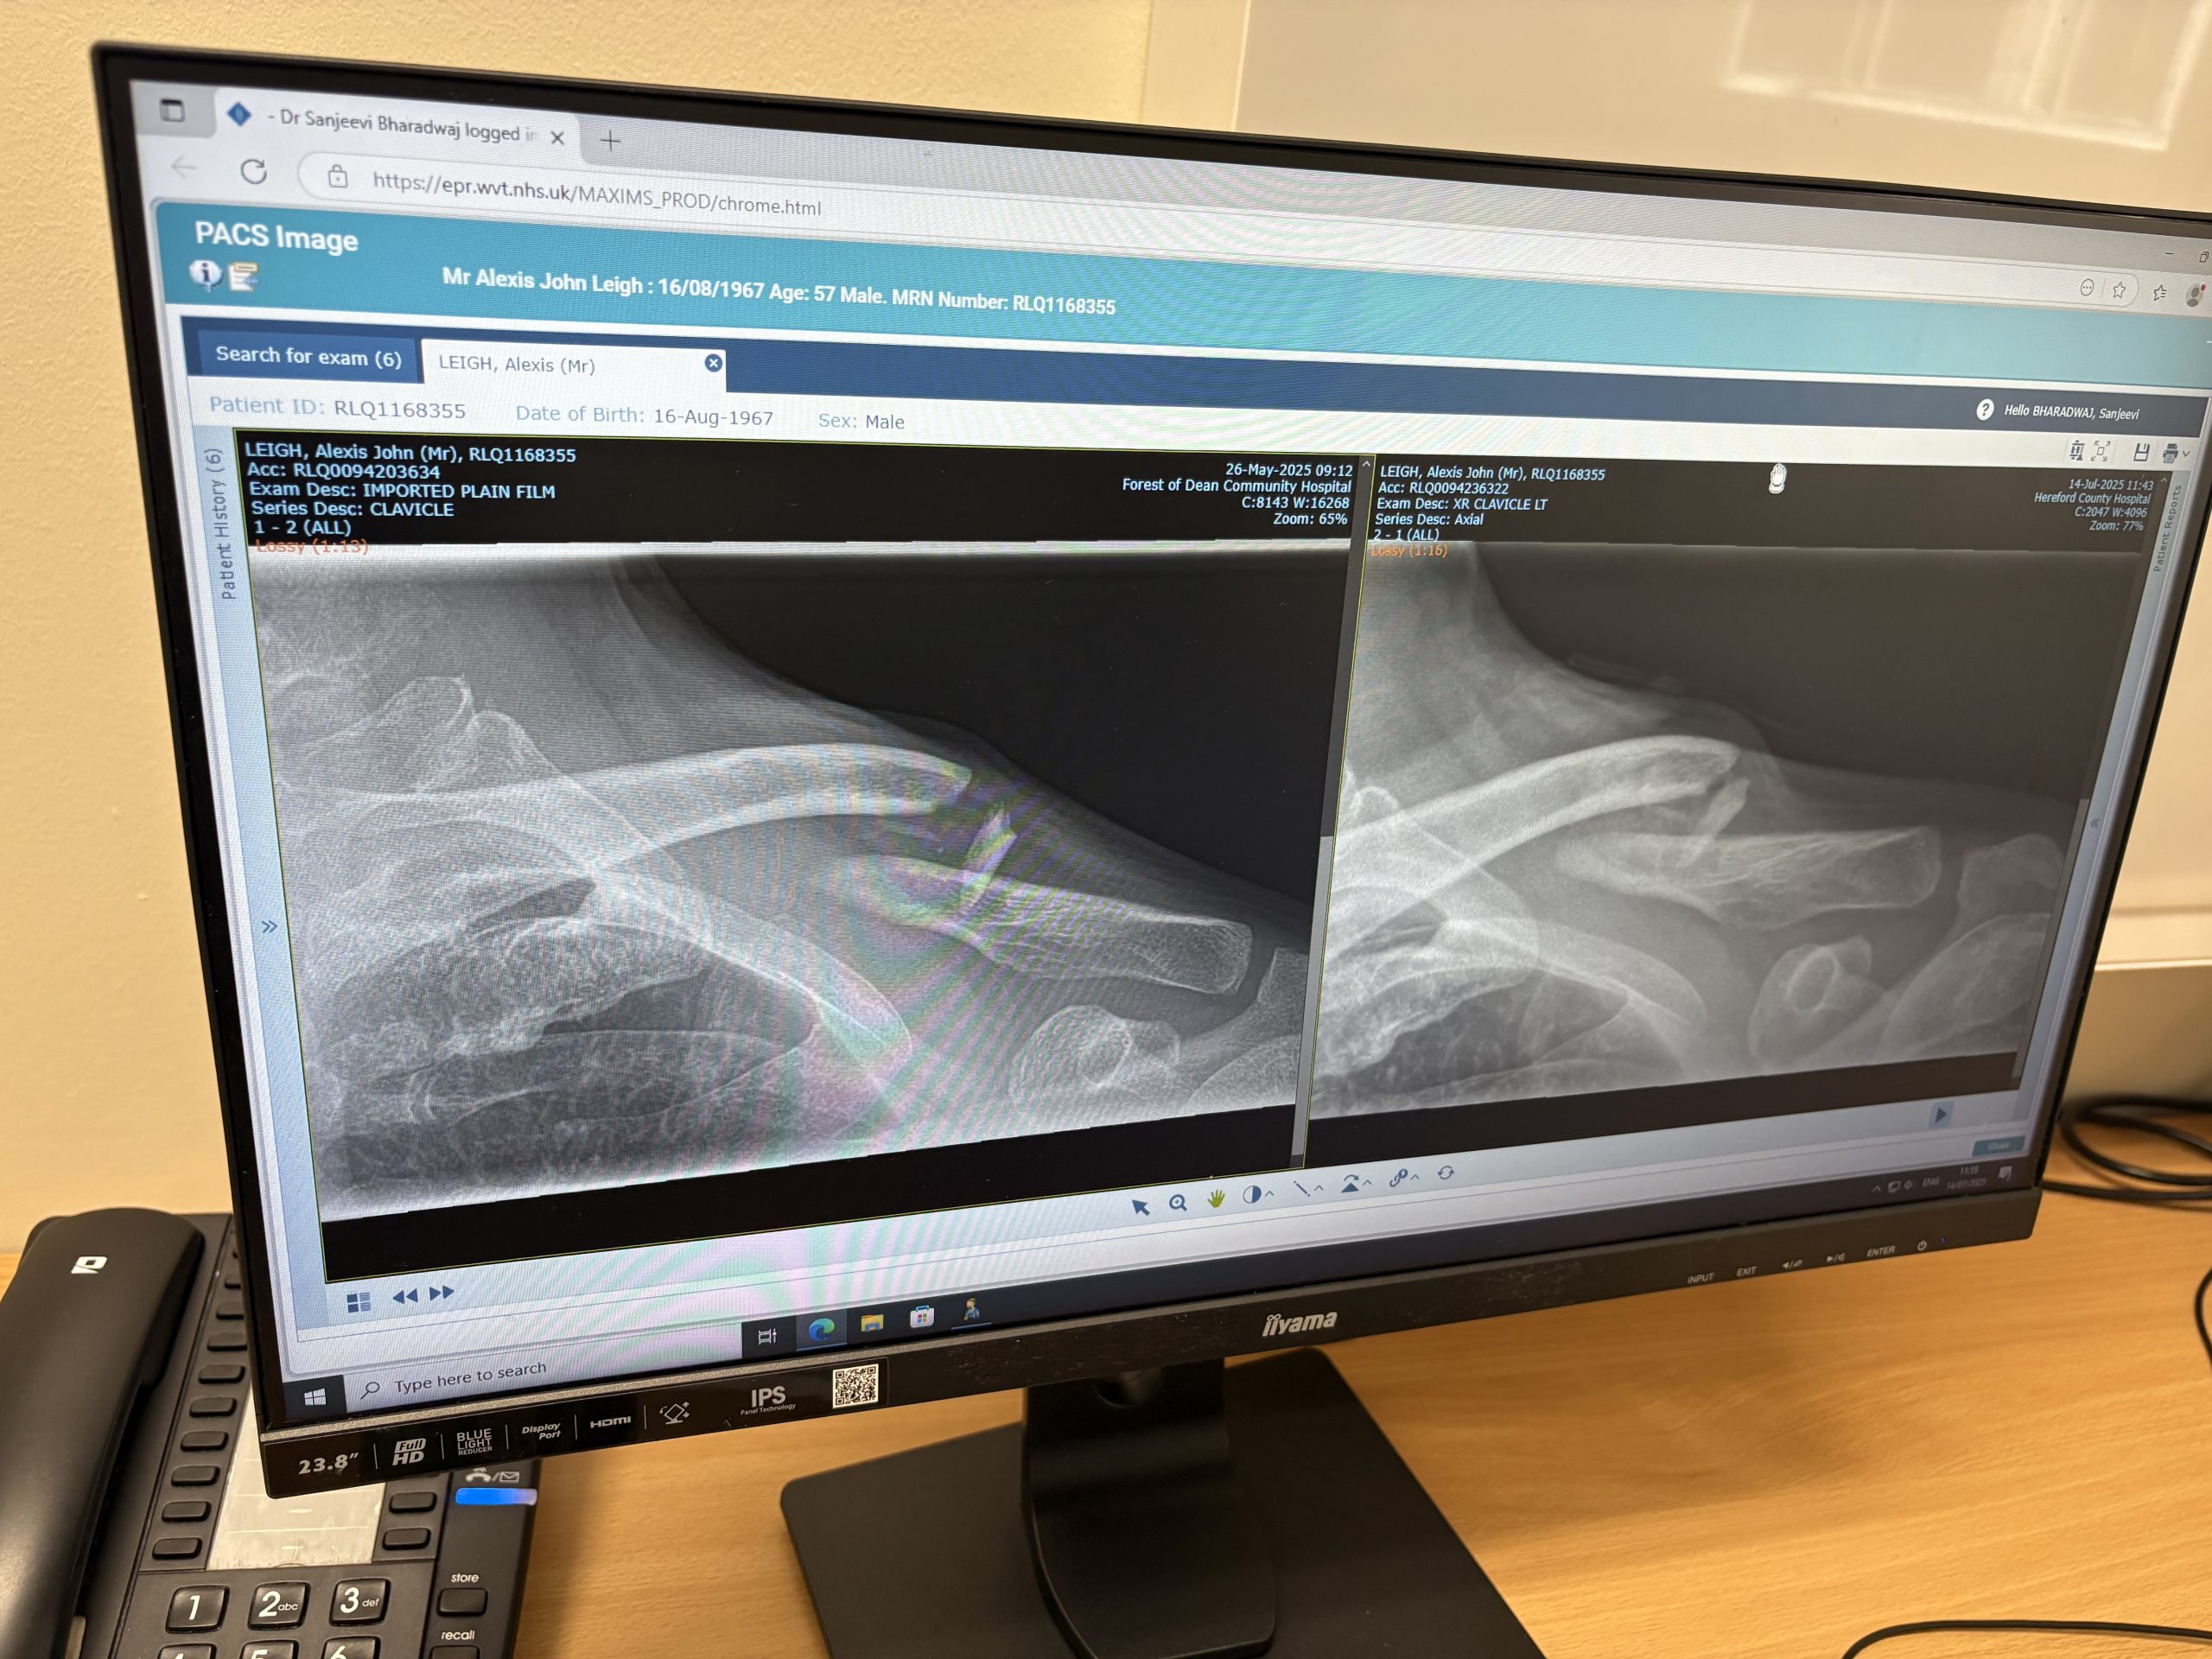

Original break on the left, 7 week x-ray on the right. What’s hard to see is the shadow between the break showing a healthy growth of new bone. Just not quick enough for Mr Impatient here. Not even close.